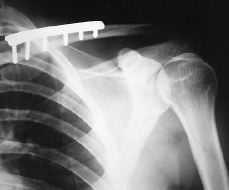

Paciente varón de 29 años de edad, sin antecedentes de interés, que sufre caída accidental con traumatismo directo sobre hombro izquierdo, presentando dolor e impotencia funcional en dicha articulación. A la exploración física se objetivó dolor y deformidad en hombro izquierdo con signo de la tecla positivo, sin déficit vasculonerviosos distales. En las radiografías realizadas (Fig. 1) se apreció una fractura de tercio medio de clavícula izquierda desplazada, asociada a luxación acromioclavicular tipo II de la clasificación de Tossy y cols.6,7 Fue intervenido quirúrgicamente, realizando reducción y fijación de la fractura de clavícula izquierda con placa DCP, así como revisión de los ligamentos acromioclaviculares, en los que se comprobó su integridad y fijación de la articulación acromioclavicular con dos agujas de Kirschner (Fig. 2). El paciente fue inmovilizado con sling, cursando el postoperatorio sin ningún incidente; las agujas se retiraron a las 4 semanas (Fig. 3) y tras un período de 3 años de seguimiento se observó una movilidad completa e indolora, alcanzando arcos articulares en el hombro afectado comparables al lado sano, así como unos resultados funcionales en los que se alcanzó una puntuación máxima en la escala de Constant2,25,20 (25/30) (Figs. 4 y 5).

Figura 1. Rx preoperatoria en la que se aprecia ensanchamiento de la articulación acromioclavicular.